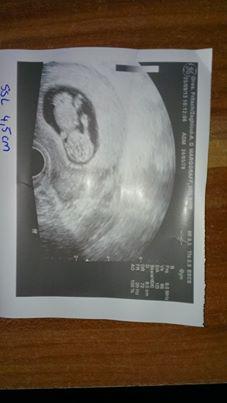

Hallöchen bin 10+6 heute und der Toxo Test war negativ, naja heißt also aufpassen... sonst ist alles bestens Baby ist jetzt 4,5 cm groß Herzchen schlägt kräftig, hat er geschlafen sich aber vom US gestört gefühlt und dann richtig Action gemacht. Also alles in allem super gelaufen. Wünsche den anderen auch so tolle Neuigkeiten. Und alles Gute.

Bild zu zurück vom FA - Forum für April - Mamis

Was für ein tolles bild..bin am Dienstag dran, dann bin ich soweit wie du jetzt;). Super das alles in Ordnung ist freu mich für dich!!

Was für ein tolles Bild! Weiterhin alles Gute